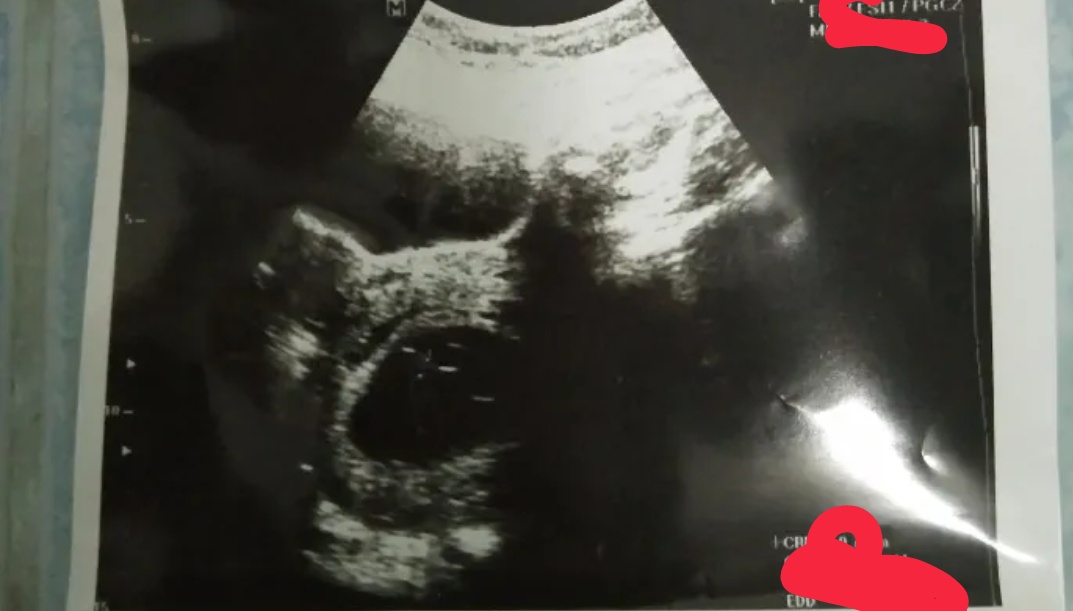

เมนมาครั้งสุดท้ายตอน 26ส.ค.64 ตรวจครั้งแรกตอน 7ต.ค.64 พอวันที่ 12 พ.ย.64ไป ซาวดูปรากฏดังภาพหมอว่ายังไม่ชัด แบบนี้มีโอกาศแท้งไหมครับ